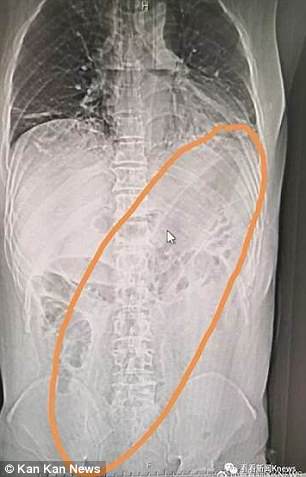

Den stora grönsaken hade flyttats upp längs den 50-åriga mannens tarmar och tillslut nått den övre buken, enligt sjukhuset.

Läkarna hävdade att när de hittade auberginen hade den nästan nått mannens hjärta.

Rapporten hävdade också att mannen hade lidit av svullnad och smärta i magen i två dagar innan han sökte vård på sjukhuset, en medicinsk rapport visade att en CT-skanning bekräftade att mannen hade en fotlångt främmande föremål i övre buken.

Röntgen visade att föremålet hade fastnat i en diagonal position och att mannens lungor var inflammerade.